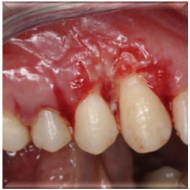

计划切除增生牙龈。由于增生范围较大,拟利用腭侧牙龈进行软组织修复。